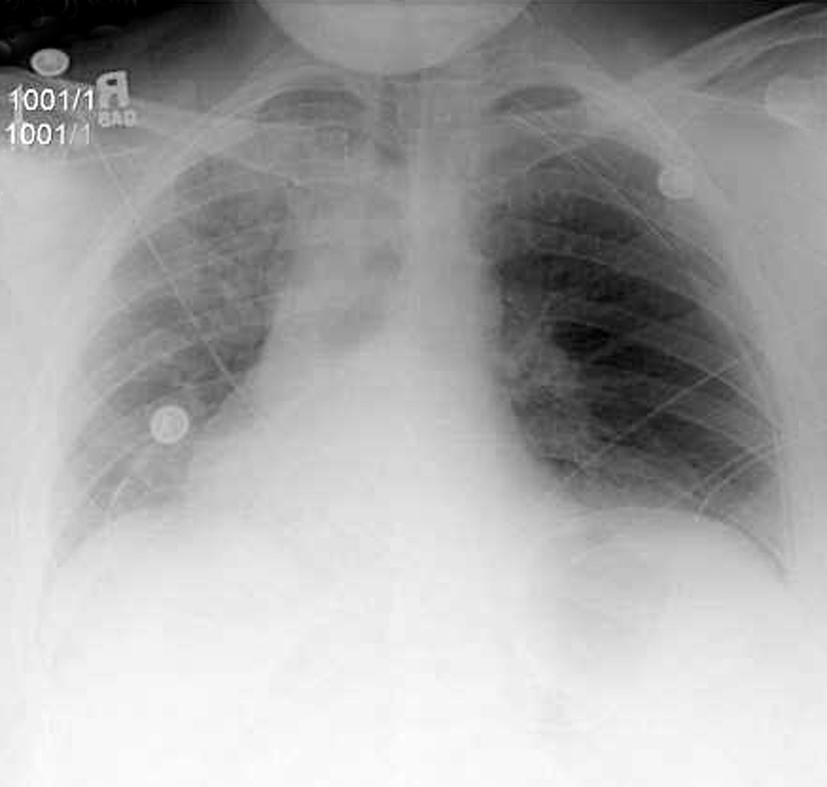

The left dome was opened anteriorly and towards the periphery following the line of insertion into the chest wall, in order to avoid injury to the major branches of the phrenic nerve. The transverse colon and the spleen were displaced inferiorly through the opened diaphragm. The colon was massively distended and was carefully reduced into the abdominal cavity. The redundancy of diaphragmatic dome was such that the posterior edge had to be trimmed removing an elliptical segment of muscle of 14 x 8 cm in size. The diaphragm was reconstructed overlapping the two edges of the opened muscle with interrupted, size O, nonabsorbable U-shaped sutures in a “double-breasted” reconstruction technique, reinforced by a second running layer (Figure 4).

The repair is most easily performed through the chest, with a lateral thoracotomy at the 7th or 8th intercostal space [4]. The strategy of surgical repair has to be adapted to each specific case. The approach through the chest makes the correction of the diaphragm technically easier. It provides exposure over the convexity of the diaphragmatic dome and allows a more precise estimation of the tension that is needed to obtain an optimal correction. The goal of surgical correction is to place the diaphragmatic leaflet in a position of maximum inspiration which relieves compression on the lung parenchyma and allows its re-expansion [4, 10, 11]. The repair of the diaphragm is accomplished by plication of the diaphragm or by imbrication. Imbrication is performed by opening the diaphragmatic dome and overlapping the two edges of the muscle (Figure 4). When the diaphragm is substantially elevated, resection of a portion of diaphragm is required, followed by reconstruction with a double breasted suturing technique.